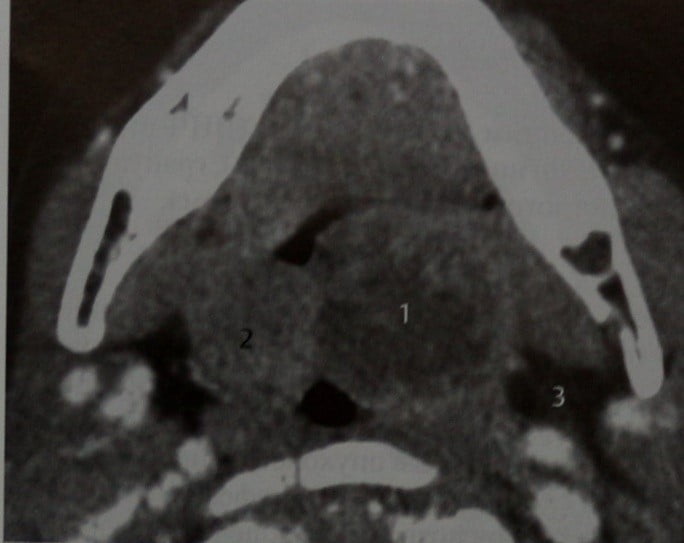

КТ диагностика тубоовариального абсцесса: Подходы и изображения

Раздел: Объективный взгляд